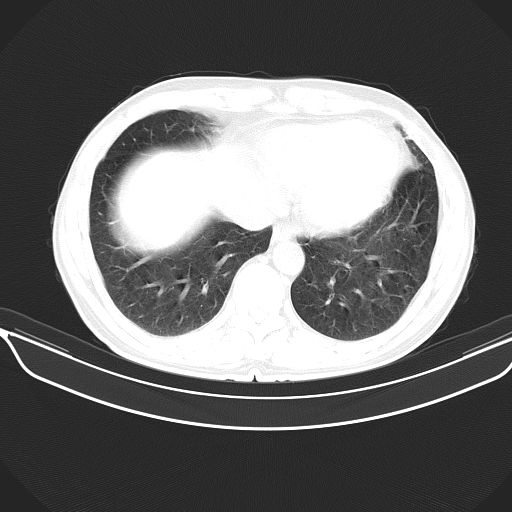

以下是引用shuiyuan在2010-3-1 10:45:00的发言:[br]考虑左肺上叶中心型肺癌伴阻塞型炎症,邻近胸膜受侵。

以下是引用心路寻觅在2010-3-1 10:23:00的发言:[br]1、考虑左肺上叶周围型肺癌[br]2、右上肺陈旧性病灶。[br][br][本贴已被 心路寻觅 于 2010-3-1 10:40:18 修改过]